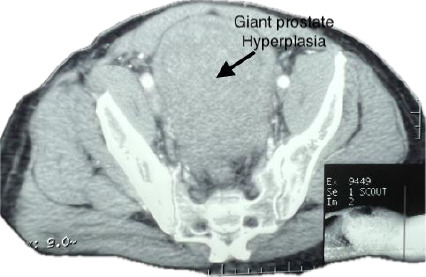

Giant prostate hyperplasia is defined as prostate hyperplasia with a weight greater than 500 grams. This condition is rare. We present the management of a case of giant prostate hyperplasia (541 grams on CT scan) with a surgical enucleated volume of 800 grams in a patient who presented with haematuria. An abdominal-pelvic CT scan was required to differentiate it from a suspected bladder tumour. This case was successfully managed with a favourable outcome following open transvesical prostatectomy, ensuring minimal blood loss. This case report and review provide an update on the management of giant prostate hyperplasia, with emphasis on the prevention and management of haemorrhage.